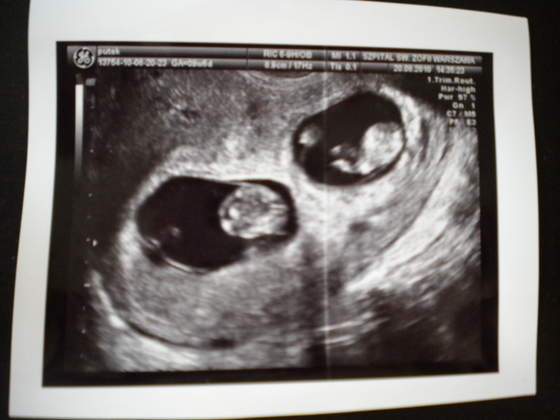

ja od wczoraj mam moich chlopaczkow w domu, pierwsza noc juz za nami oczywiscie nie przespana ale jest super) jestem taka szcesliwa, chlopaczki sa przekochane

karmie ich butelka ale moim pokarmem bo nie chca za bardzo z cyca jesc, troszke ich to meczy i szybko usypiaja. generalnie troche pracy jest nie bede ukrywac ale kurde nie zameinilabym sie z zadna pojedyncza mama